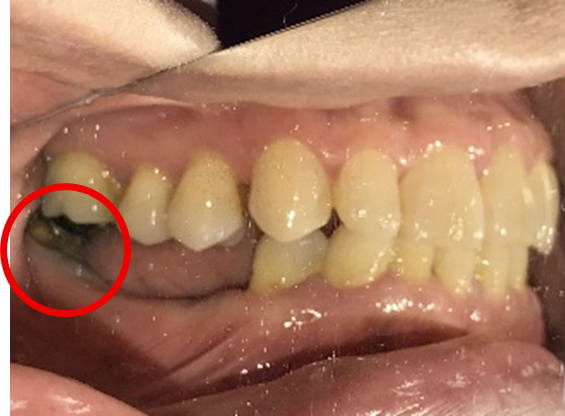

Before

赤丸は抜歯しました

治療内容

レントゲンで詳しく診てみると、左下の動いている歯、右下の一番奥は、保存することができず、抜歯しました。左下の抜歯したところは、骨造成後、左に2本、右に2本インプラントを埋入しました。

所感

左下の抜歯したところは、大きく骨が欠損していましたので、骨造成をしました。5か月間待ってからインプラントを埋入しました。骨をきちんと作ってから埋入して、正解でした。今回もX-Guideを使った埋入で、安心安全に行うことできました。